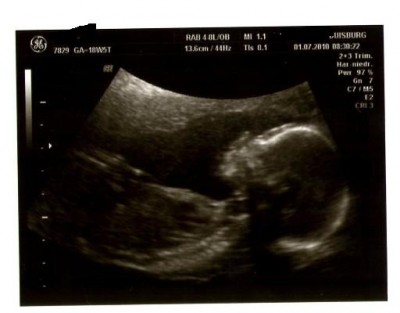

Ich bin echt froh das mein FA immer 3D macht-nun ja außer gestern, warum auch immer!

@conny: Ich stell mal gleich ein Bildchen von unserer Madame rein.Ich wollte getsren eigentlich schon aber war mir doch sehr unsicher da hier leider wieder ein paar negativs reingeflattert sind!